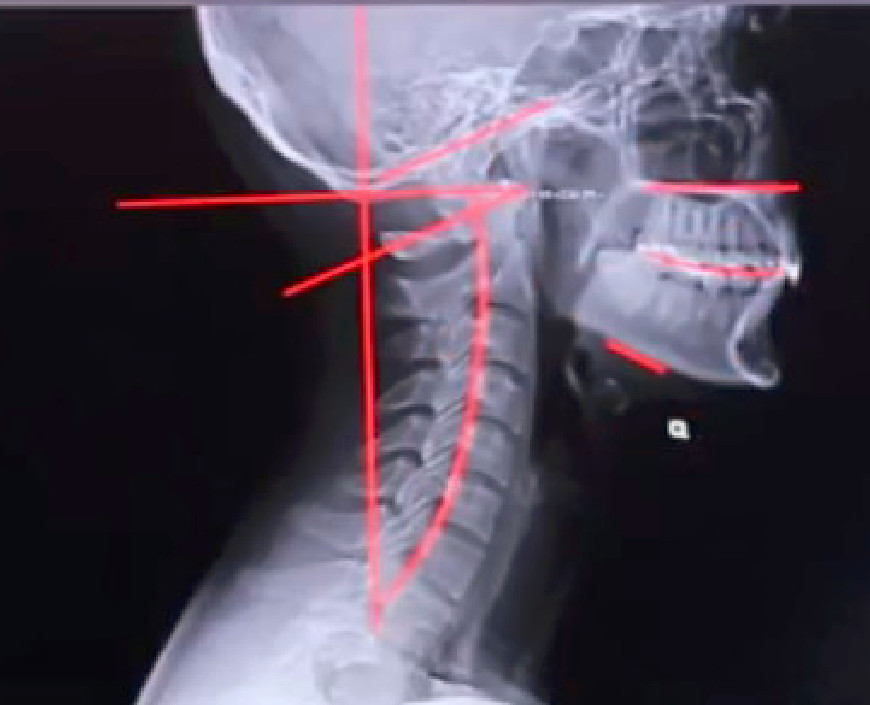

Podstawą diagnozy jest badanie kliniczne oraz zdjęcie RTG kręgosłupa w projekcji AP i bocznej. Chiropraktyk lub terapeuta manualny ocenia ustawienie miednicy, rotację kręgów i napięcie tkanek miękkich.